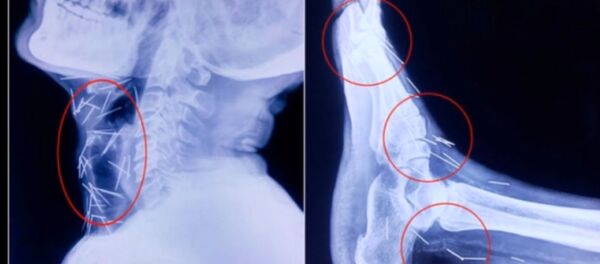

Le danger de tenir dans sa bouche des objets pointus tels que des aiguilles a été démontré par un cas rare décrit par des médecins américains dans un rapport publié dans le Journal of Emergency Medicine.

Ce cas montre le danger potentiel que présentent les objets pointus, tels que les arêtes de poisson, en cas d’ingestion. Ils sont le plus souvent éliminés naturellement dans le transit intestinal. Cependant, le risque de leur migration persiste et les objets pointus avalés, même s’ils ne dépassent pas une longueur de cinq centimètres, qui normalement ne donnent pas de complications, devraient sans doute être retirés par précaution, suggèrent les spécialistes.

Il arrive aussi, bien que rarement, que des morceaux d'aiguille migrent vers le cœur par voie intraveineuse après l'utilisation de stupéfiants ou des procédures d’acupuncture.